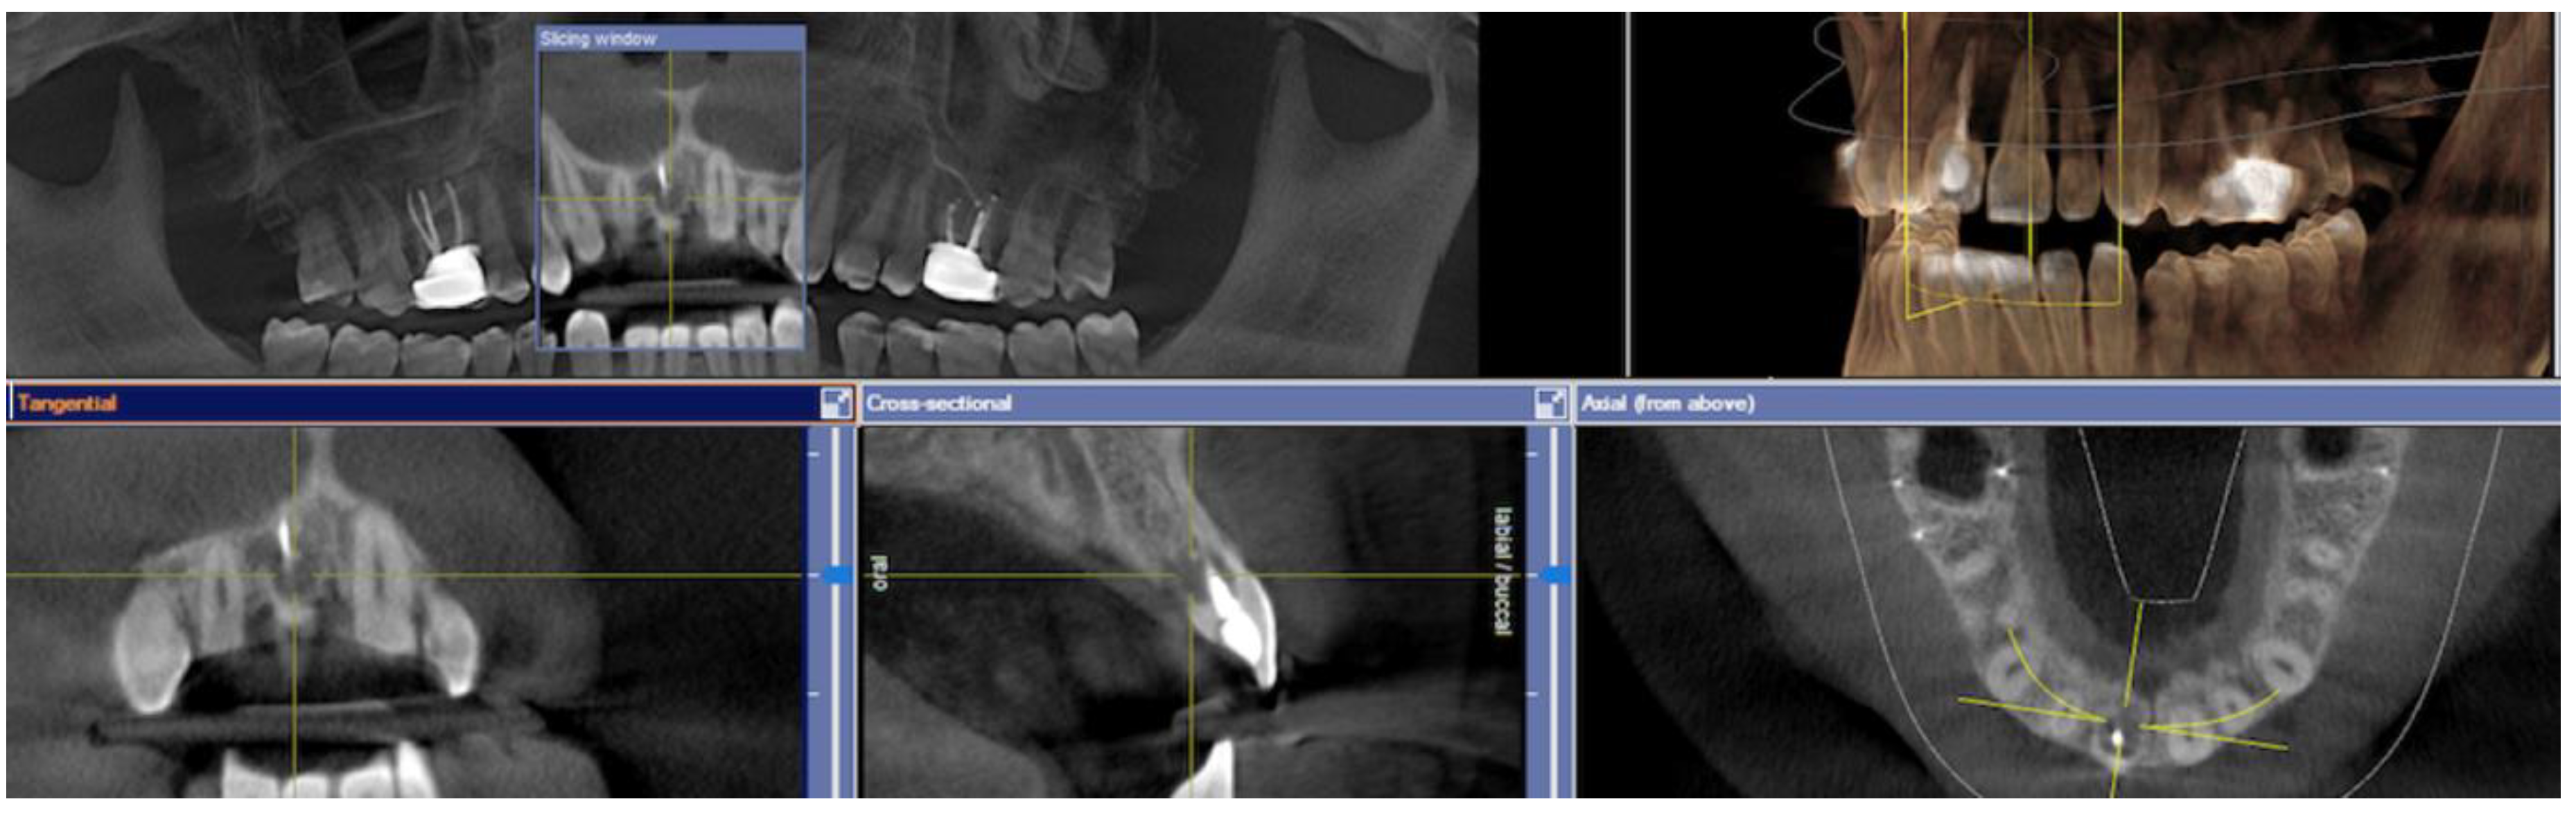

2.2. Pre-Surgical Stage